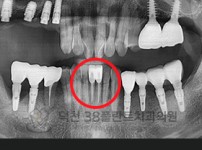

치료전후